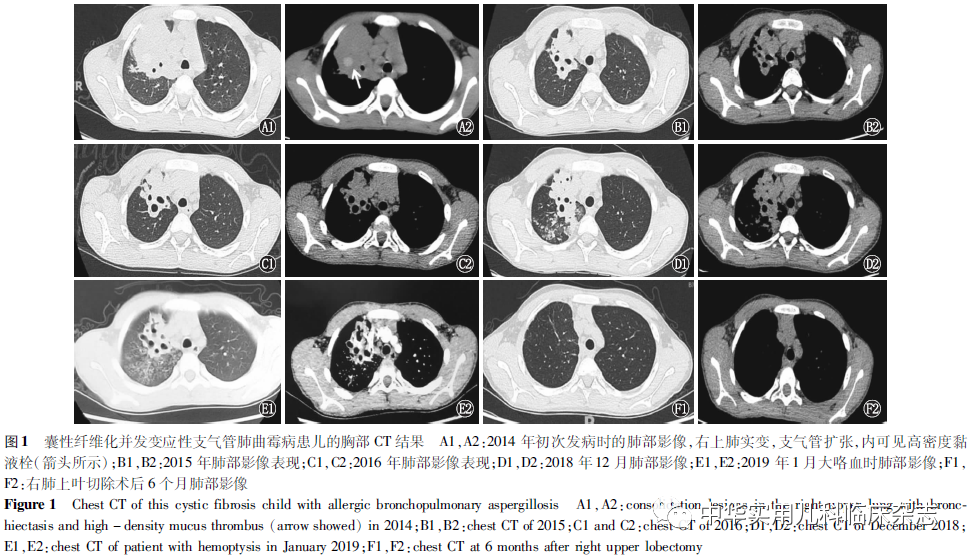

临床资料回顾性分析。患儿,男,15岁4个月,因“间断咳嗽伴咳痰6年余,加重22 d”于2021年5月入住首都医科大学附属北京儿童医院呼吸一科。患儿6年前(2014年,8岁)因间断咳嗽咳痰来诊,血嗜酸性粒细胞增高,血清总IgE>500 IU/mL,烟曲霉特异性IgE及IgG阳性,胸部CT提示右上肺实变伴中心型支气管扩张(图1 A1、A2),且病程中均发现高密度黏液栓,诊断为ABPA,给予泼尼松口服[起始剂量为2 mg/(kg·d)]及伏立康唑[4 mg/(kg·次),2次/d]治疗,总疗程9个月。期间患儿多次因反复咳嗽、咯痰,行支气管镜灌洗治疗,随访肺部影像逐渐好转(图1 B1、B2、C1、C2)。进一步筛查患儿的基础疾病,查汗氯:89 mmol/L,基因检测示CF跨膜转导调节因子(CFTR)基因复合杂合突变(c.2909G>A,来自父亲;c.3310G>T,来自母亲),诊断CF并发ABPA。3年前(2018年,12岁余,即确诊ABPA后第4年),患儿血清总IgE及嗜酸性粒细胞计数水平上升至基线水平的2倍以上,支气管肺泡灌洗液中找到菌丝,胸部CT提示右侧支气管扩张加重,右上病变包绕肺动脉 (图1 D1、D2),之后出现大咯血(图1 E1、E2)。再次给予口服伏立康唑联合5-氟胞嘧啶[100 mg/(kg·d),分4次]抗真菌治疗,并经胸腔镜行右上肺叶切除术。术后患儿咳嗽、咯痰较前好转,咯血消失,血清总IgE及嗜酸性粒细胞降至正常,影像学中心型支气管扩张消失 (图1 F1、F2),监测肺功能持续存在小气道功能减低,后期存在混合性通气功能障碍。1个月前(2021年,15岁余)患儿再次出现咳嗽加重,查血嗜酸性粒细胞及IgE再次升高,肺CT提示左上肺实变伴支气管扩张(图2 A1~A4),收住院。患儿6月龄后开始出现反复呼吸道感染。患儿系第1胎,第1产,足月顺产,出生体重为4 kg,父母身体均健康,父母均否认有家族遗传病史。患儿已接种”乙型肝炎、卡介苗、百白破、脊髓灰质炎、麻疹”等疫苗。体格检查:体温36.5 ℃,脉搏88次/min,呼吸18次/min,血压108/67 mmHg(1 mmHg=0.133 kPa),经皮血氧饱和度0.99,身高175.5 cm,体重52.5 kg,体重指数(BMI)17 kg/m2,神志清楚,精神反应可,呼吸平稳。未见鼻翼扇动及吸气性三凹征。双肺呼吸音粗,未闻及干湿性啰音。心腹及神经系统查体未见异常。杵状指(+)。诊治经过及随访:入院后查血嗜酸性粒细胞绝对值0.9×109/L,嗜酸性粒细胞百分率 8.9%,IgE 1 720 IU/mL,过敏原皮肤点刺试验:产黄霉素(+),黑曲霉/多价真菌(+),烟曲霉特异性IgE 44.8 kUA/L(A指变应原)(4级)阳性,烟曲霉特异性IgG 323.62 AU/mL,阳性;常规肺功能轻度混合性通气功能障碍(小气道功能重度减低);支气管镜检查及灌洗治疗,镜下见支气管各支广泛分泌物增多,左侧为著,有黏液栓阻塞,灌洗出褐色阻塞物(图3);(支气管灌洗液)涂片散在退变的吞噬细胞(约81%),少量脱落的上皮细胞(约10%)、淋巴细胞(约6%),偶见嗜酸性粒细胞(约3%),可见夏科雷登结晶(图4)。支气管灌洗液培养铜绿假单胞菌,烟曲霉。确诊ABPA后予泼尼松0.5 mg/(kg·d),伏立康唑抗真菌,治疗1周后复查支气管镜好转,共住院治疗 17 d,复查嗜酸性粒细胞正常,IgE 1 440 IU/mL。院外继续激素及伏立康唑治疗。现治疗7个月后患儿恢复良好,复查嗜酸性粒细胞正常,IgE 320 IU/mL,复查肺部CT及支气管镜均较前好转(图2 B1、B2;图3),支气管灌洗液培养提示金黄色葡萄球菌。本研究通过医院医学伦理委员会批准(批准文号:2020-Z-135),患儿监护人知情同意。